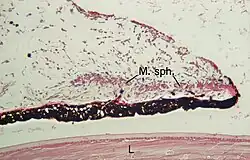

Microanatomy

From anterior (front) to posterior (back), the layers of the iris are:

- Anterior limiting layer

- Stroma of iris

- Iris sphincter muscle

- Iris dilator muscle (myoepithelium)

- Anterior pigment epithelium

- Posterior pigment epithelium